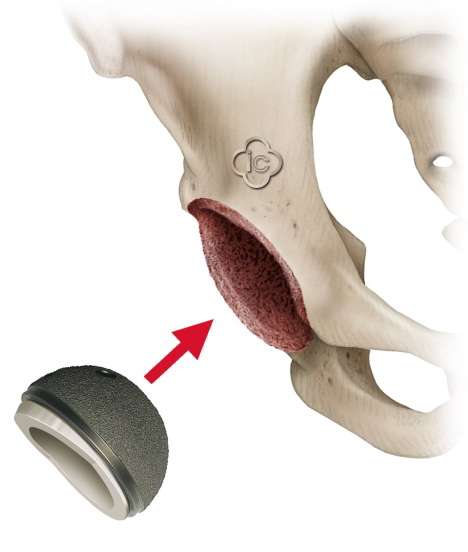

Hüftpfannen zementiert oder zementfrei befestigen?

In der orthopädischen Gelenk-Klinik kommen zementierte Pfannen fast nicht mehr zum Einsatz. Die Zementschicht stellt immer eine kritische Komponente in der Befestigung dar. Wir arbeiten vorrangig mit zementfreien "Press-Fit"-Pfannenkomponenten. Diese Pfannenprothesen werden in den vorbereiteten Beckenknochen geklemmt und erhalten dadurch bereits unmittelbar nach der OP einen festen Sitz. Zusätzlich wächst in den Wochen nach der Operation der Beckenknochen in die raue Oberfläche der Hüftpfanne ein.

Aufbau des Pfanneninlays

Die Hüftpfanne der Prothese enthält das Pfanneninlay. Das ist der eigentliche Gleitpartner des Oberschenkelkopfes. Es existiert eine Vielzahl von Modellen und diese Vielfalt ist berechtigt: Sie gibt uns Orthopäden die Möglichkeit, mit der spezifischen Auswahl des Prothesenmodells genau auf den Patienten einzugehen.

Die Hüftpfanne wird heute in der Regel zementfrei implantiert. Die zementierte Hüftpfanne setzen wir nur sehr selten ein, da es dann vor allem bei jungen und aktiven Patienten öfter zu einer Lockerung der Prothese kommt als bei der zementfreien Variante.

Die künstliche Gelenkpfanne ist ein einteiliges System aus einer Metallschale mit einem Kunststoffinlay, z. B. Polyethylen mit oder ohne aufgebrachte Metallnetzstruktur. Das Inlay kleidet also die Hüftpfanne aus, ist Teil der Gleitpaarung und bildet das gleitende Gegenstück zum Kopf der Hüftprothese.